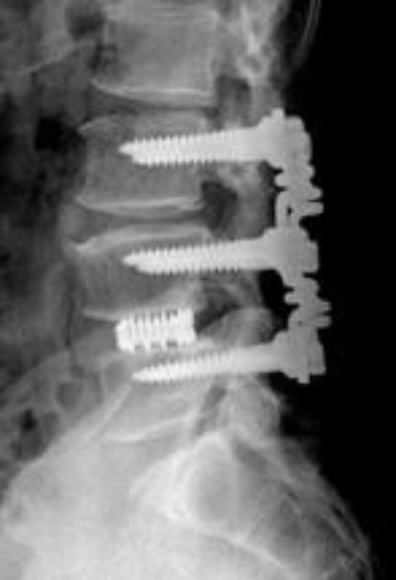

척추협착증과 같은 퇴행성 척추질환 치료에 널리 쓰이는 기존 척추고정술의 합병증을 크게 줄일 수 있는 새로운 치료술이 국내 의료진에 의해 개발됐다.

광혜병원 척추운동역학연구소 박경우 소장팀은 스프링 형태의 척추 고정기기인 ‘바이오플렉스(Bio-flex)’를 이용해 고정수술 후에도 척추 마디간 분절운동을 가능하게 하는 연성 척추고정술을 개발했다고 최근 밝혔다.

현재 대부분의 척추수술에 사용되고 있는 강성 척추고정술은 문제가 있는 척추뼈 마디를 단단한 쇠막대와 볼트너트로 고정시키는 방식이다. 이 경우 고정된 척추 마디 간의 유연성이 떨어지기 때문에 동작에 따라 상하 척추 마디에 더 많은 힘이 가해져 2차 퇴행을 유발하는 등 부작용을 일으키기 쉬운 문제가 있었다. 실제로 이 때문에 수술 환자의 46%가 5년 이내에 재수술을 받는 것으로 알려졌다.

이에 비해 이번에 국내에서 개발된 연성 척추고정술은 문제가 있는 척추와 척추 사이를 스프링 형태의 고정장치로 지지하는 방법으로, 수술 후 척추 유연성을 정상 척추의 85%까지 회복시킬 수 있을 뿐 아니라 척추의 충격을 스프링을 통해 흡수시켜 수술 부위의 퇴행 속도를 최소화하며, 척추 고정 부위의 안정성도 크게 높인 것으로 평가되고 있다.